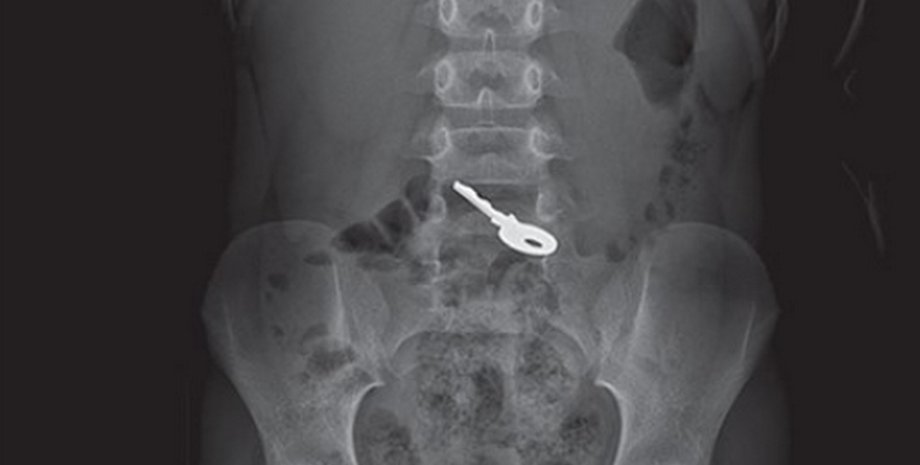

Шестилетний ребенок проглотил ключ | Фото: Jam Press

Несмотря на отсутствие физических симптомов, в приемном отделении был проведен рентген, который показал инородное тело в животе. Поскольку ключ не вызвал осложнений, медики решили не проводить операцию, а ограничиться наблюдением.

Специалисты регулярно делали рентген, чтобы отследить перемещение объекта. Через 48 часов снимки показали, что ключ уже добрался до кишечника.